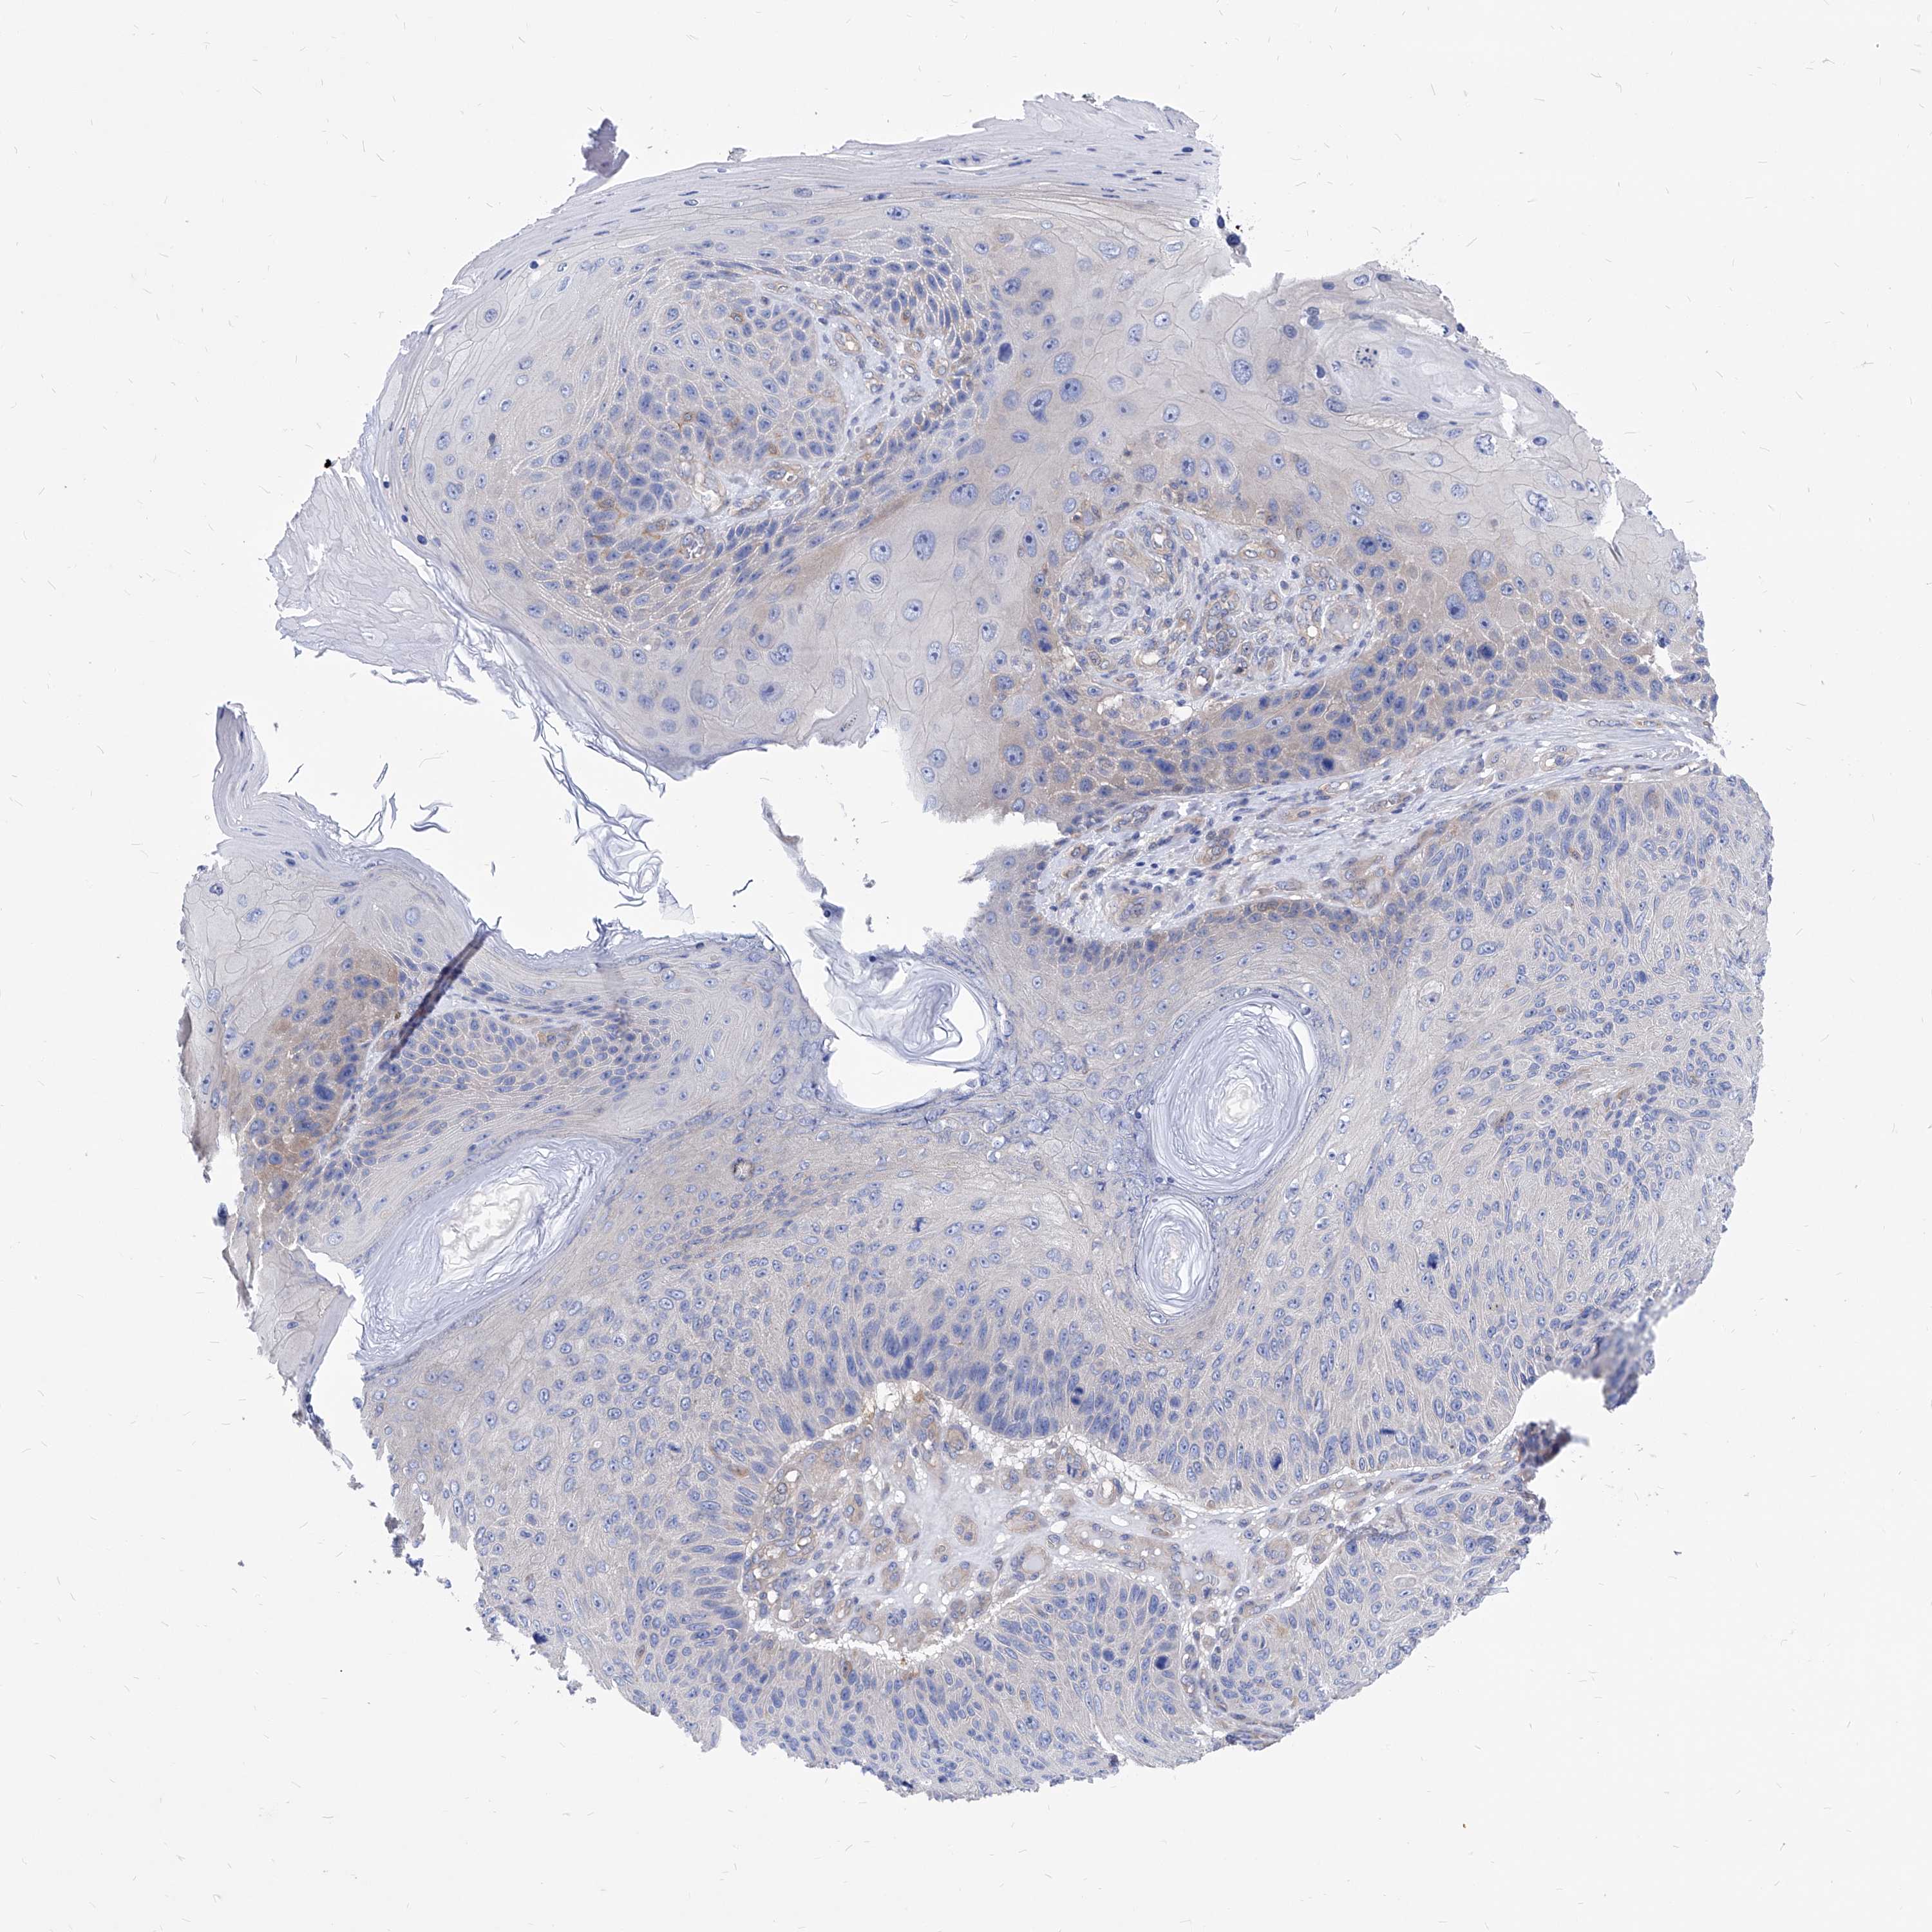

CANCER SKIN CANCER Show tissue menu

SKIN CANCER - Protein expressioni

A mouse-over function shows sample information and annotation data. Click on an image to view it in a full screen mode. Samples can be filtered based on level of antibody staining by selecting one or several of the following categories: high, medium, low and not detected. The assay and annotation is described here.

Antibody stainingi

Antibody staining in the annotated cell types in the current human tissue is reported as not detected, low, medium, or high, based on conventional immunohistochemistry profiling in selected tissues. This score is based on the combination of the staining intensity and fraction of stained cells.

Each image is clickable and will lead to virtual microscopy that enables deeper exploration of all samples and also displays staining intensity scores, fraction scores and subcellular localization as well as patient and tissue information for each sample.

HPA030419

HPA030420

HPA030422

CAB025196

CAB080286

CAB080287

Basal cell carcinoma

Squamous cell carcinoma, NOS

Squamous cell carcinoma, metastatic, NOS